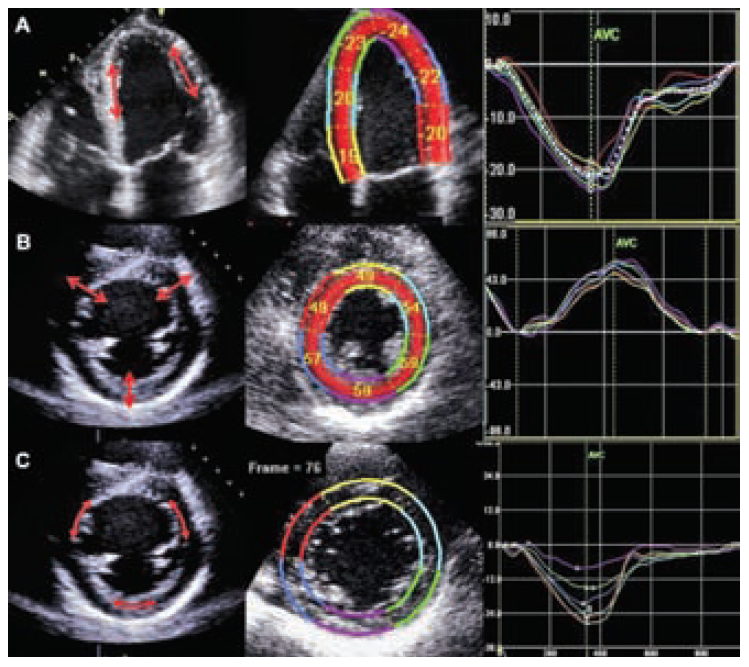

Сердечная мышца, как известно, состоит из трех разнонаправлено ориентированных слоев – наружного косого, среднего циркулярного и внутреннего продольного. Благодаря скоординированному сокращению всех слоев в здоровом сердце обеспечивается максимально эффективный сердечный выброс. Специальная ультразвуковая методика, получившая название «speckle tracking» (в переводе от англ. – отслеживание точек) позволяет изучать амплитуду движения небольших участков – точек в миокарде. Процент изменения расстояния между точками называется деформацией. Для изучения трехмерной структуры сердце оценивается в 5 проекциях, а ЛЖ делится на 17 сегментов. Это позволяет получить информацию о сократительной функции миокарда (деформации) в продольном, радиальном и циркулярном пространственных направлениях. Деление на сегменты дает представление о локальной деформации по-сегментарно в разные периоды цикла, а также позволяет учитывать параметры ротации и скручивания ЛЖ (рис. 1).

Рис.1. Определение продольной деформации (А), радиальной деформации (В)и циркулярной (С)методом speckle-tracking ЭхоКГ [14]. В левой части рисунка стрелки указывают направление деформаций. В средней части – значения деформаций по сегментам (кроме циркулярной). В правой части – кривые деформаций. Нормальные значения для продольной деформации -19,7% (95% ДИ: от -20,4% до-18,9%), для радиальной 47,3% (95% ДИ: от 43,6% до 51,0%)и циркулярной -23,3% (95 % ДИ: от -24,6% до -22,1%)[20]. AVC – время закрытия аортального клапана.